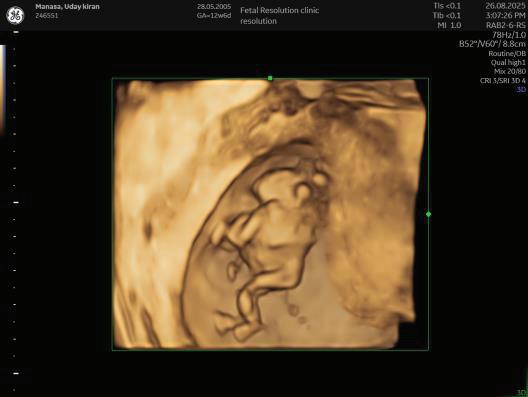

The first trimester— spanning from conception to 13+6 weeks—is no longer considered a “blind phase” of pregnancy. With the evolution of highresolution ultrasound, color Doppler and advanced biochemical screening, this period has transformed into a window of opportunity for early fetal evaluation, risk prediction and preventive strategies.

First-trimester fetal evaluation is not limited to dating the pregnancy or confirming viability—it is the foundation of predictive, preventive, and personalized obstetric care.

1. Establish viability and Confirmation of intrauterine pregnancy/ uterine integrity.

2. Accurate dating of pregnancy.

3. Early assessment of fetal anatomy.

1. EARLY PREGNANCY SCAN (6–10 WEEKS)

Indications:

1. Confirmation of pregnancy.

2. location of pregnancy.

3. Number of fetus.

4. Cardiac activity.

5. Initial dating.

6. Assessment of uterine contour to ruleout any uterine anamolies.

7. Examnation of adenexa.

Findings:

• Gestational sac at ~4.5–5 weeks-Appears as anechoic fluid filled structure surrounded by a decidual reaction (Double Decidual sac sign).

• Measure Mean sac diameter .

• Yolk sac appear around ~5–5.5 weeks.

• Embryo with cardiac activity around 6 weeks.